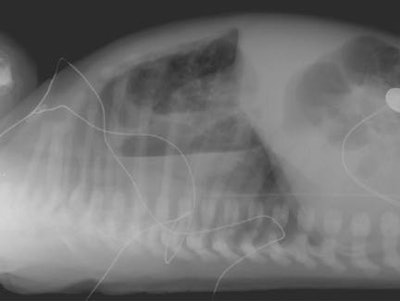

Congenital Cystic Adenomatoid Malformation:

In the case below, a newborn infant presented with repiratory difficulty, hypoxia, and cyanosis immediately following delivery. The films below were take 24 hours after delivery and demonstrate the presence multiple air filled cysts within the right hemithorax. A cross table supine exam demonstrates the presence of air-fluid levels within many of the cysts. At surgery, the patient was found to have a Type I CCAM which involved the right upper lobe.